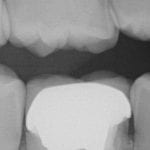

In this clinical video we demonstrate how to scan a molar preparation for the replacement of a crown with recurrent decay and open margins. The molar was root canal treated and the tissue was inflamed. the preparation was imaged and a temporary was fabricated to allow the tissue to heal properly.

The main point of this video is to show how to capture the contacts of the adjacent teeth and the deep marings